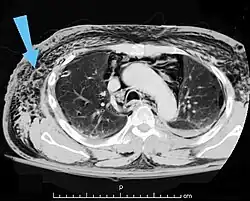

Significant cases of subcutaneous emphysema are easy to diagnose because of the characteristic signs of the condition.[1] In some cases, the signs are subtle, making diagnosis more difficult.[13] Medical imaging is used to diagnose the condition or confirm a diagnosis made using clinical signs. On a chest radiograph, subcutaneous emphysema may be seen as radiolucent striations in the pattern expected from the pectoralis major muscle group. Air in the subcutaneous tissues may interfere with radiography of the chest, potentially obscuring serious conditions such as pneumothorax.[18] It can also reduce the effectiveness of chest ultrasound.[28] On the other hand, since subcutaneous emphysema may become apparent in chest X-rays before a pneumothorax does, its presence may be used to infer that of the latter injury.[13] Subcutaneous emphysema can also be seen in CT scans, with the air pockets appearing as dark areas. CT scanning is so sensitive that it commonly makes it possible to find the exact spot from which air is entering the soft tissues.[13] In 1944, M.T. Macklin and C.C. Macklin published further insights into the pathophysiology of spontaneous Macklin's Syndrome occurring as a result of a severe asthmatic attack.